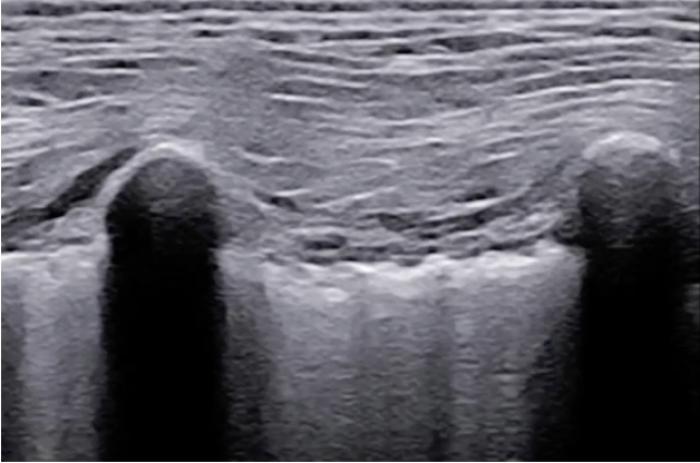

La LP es fina (por lo general inferior a 0.5 mm), regular y a pesar de tener dos componentes, la veremos como una única línea hiperecogénica.

En algunas localizaciones podemos observar una pequeña discontinuidad de la LP que corresponde a las incisuras existentes entre los diferentes lóbulos, las cuales no irán acompañadas de más signos considerados patológicos, puesto que son visibles en pacientes sanos (Figura 2) (Vídeo 1).